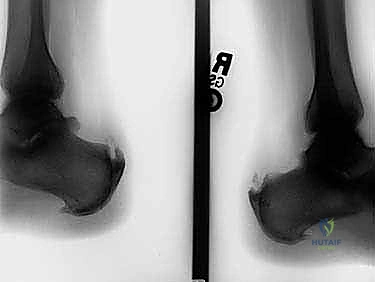

- الأشعة السينية (X-rays): ضرورية جداً في هذه الحالة لتقييم عظم الكعب، رؤية نتوء هاغلوند، وتحديد مدى التكلسات العظمية داخل الوتر.

2. عظم الكعب (Calcaneus)

هو أكبر عظام القدم، ويشكل القاعدة التي يرتكز عليها وزن الجسم في الخلف. في حالة اعتلال وتر أخيل الإدخالي، غالباً ما يتكون نتوء عظمي غير طبيعي في الجزء الخلفي العلوي من عظم الكعب، يُعرف باسم "تشوه هاغلوند" (Haglund's Deformity). هذا النتوء يعمل كشفرة تحتك بشكل مستمر بوتر أخيل مع كل حركة، مما يسرع من عملية التلف والتمزق.

- تشوه هاغلوند (Haglund's Deformity): كما ذكرنا، هو نتوء عظمي خلقي أو مكتسب في عظم الكعب يحتك بالوتر.

- النتوء العظمي المحسوس: يمكن للمريض غالباً تحسس كتلة قاسية أو نتوء في الجزء الخلفي من الكعب (تشوه هاغلوند والتكلسات).